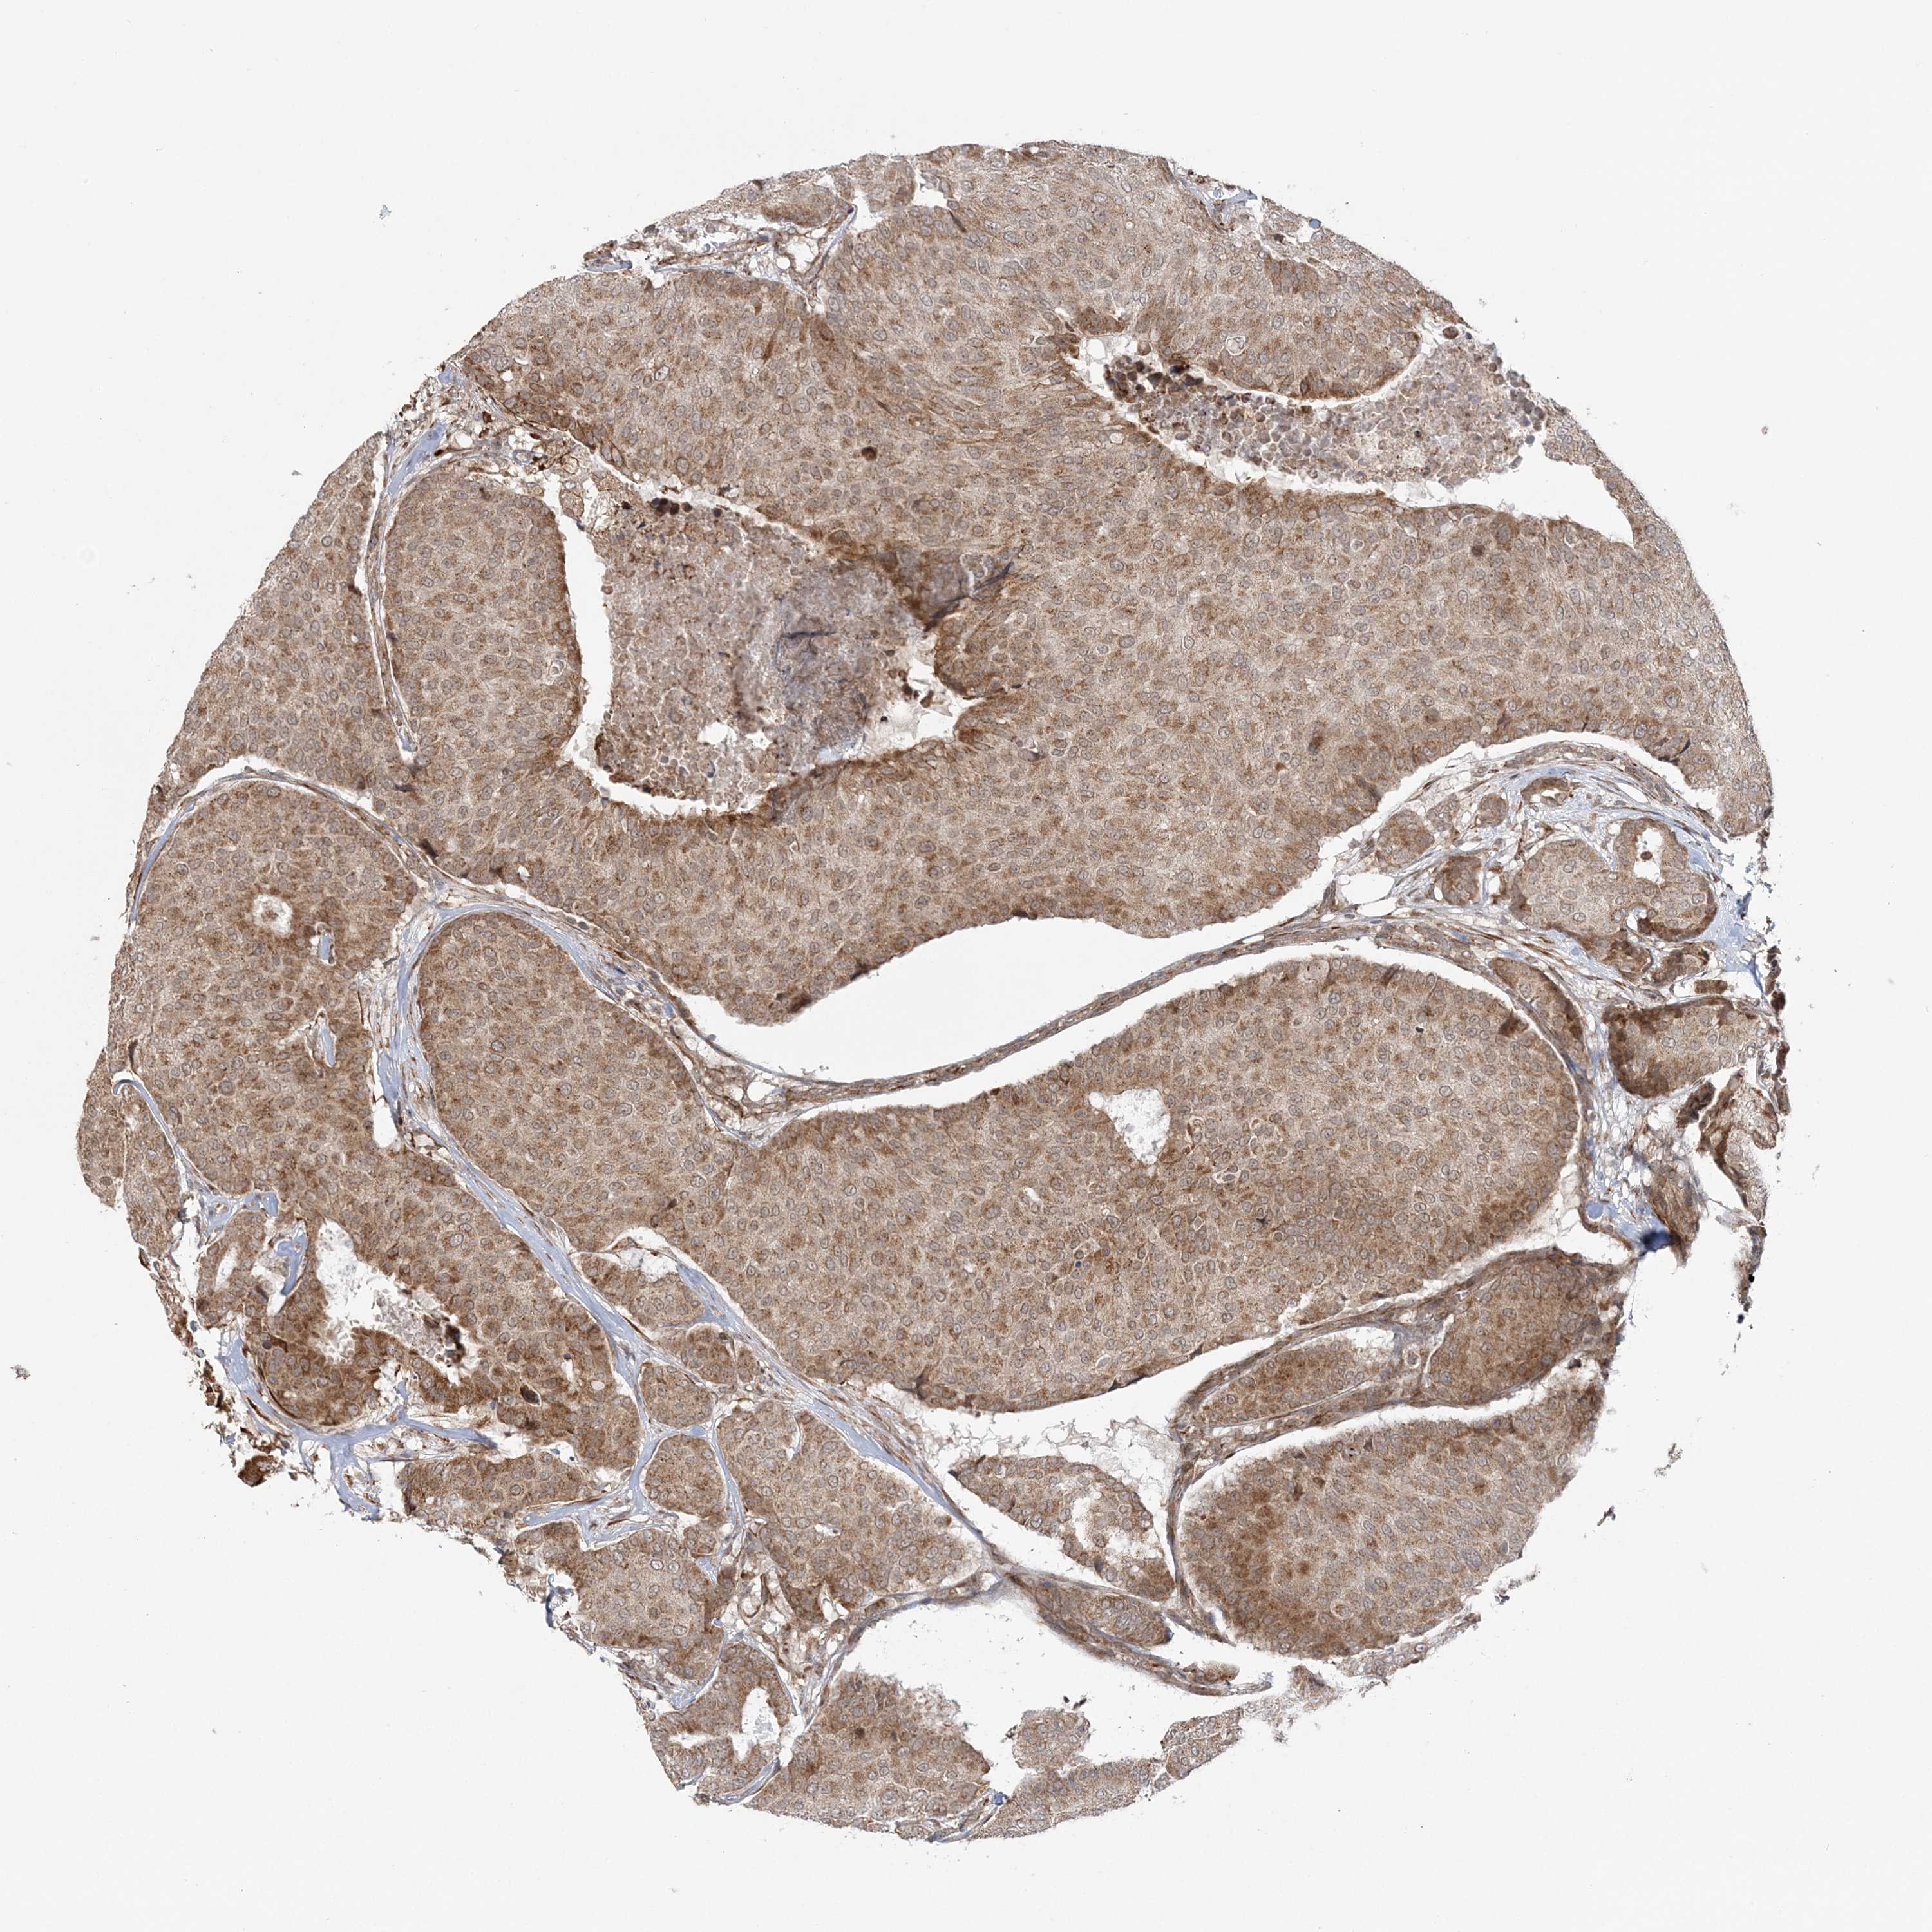

BRCA TCGA BRCA VALIDATION PROTEIN EXPRESSION

Breast cancer

Human cancer